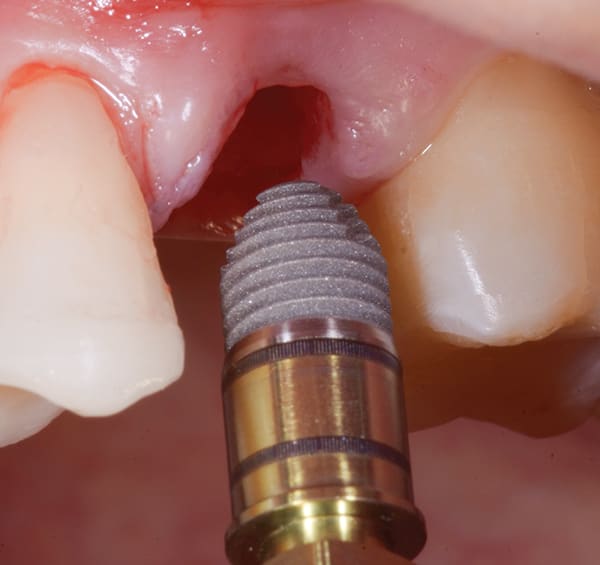

Acute Lesion

Acute lesions are thought to be reasons to use a delayed placement protocol. Use of a dual-axis, subcrestal angle-corrected implant allows the clinician to remove the lesion and atraumatically extract the tooth. This leaves good-quality bone intact while allowing the lesion to heal. The 12° Co-Axis® implant (Southern Implants) is placed into the good bone at an angle while the prosthetic platform still emerges in the correct position, occlusally parallel. As is also the case for standard implants, >70 Ncm insertion torque was readily achieved when all walls of the site were engaged, and >50 Ncm insertion torque was possible in compromised sites with atraumatic extractions using the "ice cream cone" regenerative technique to maintain soft-tissue contours.